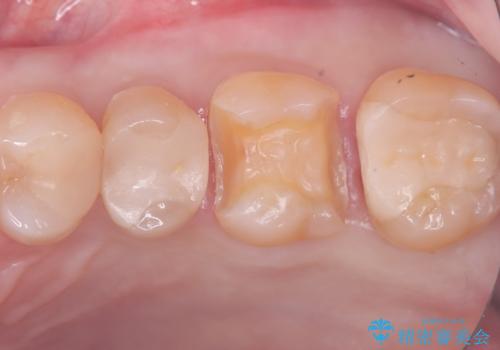

- 主訴:詰め物が欠けてしまった。

歯冠色インレーが一部欠けてしまい、他院にて部分的に樹脂のコーティング剤を付けてもらっている状態でした。

欠けている大きさが大きかったため、やり替えを提案しセラミックインレーでのやり替えとなりました。

他院にてセットしたセラミックインレーの一部が研磨では対応できない程大きく欠けてしまっていたため、やり替えとなりました。再度欠けぬよう、歯質を削り厚みを確保しています。